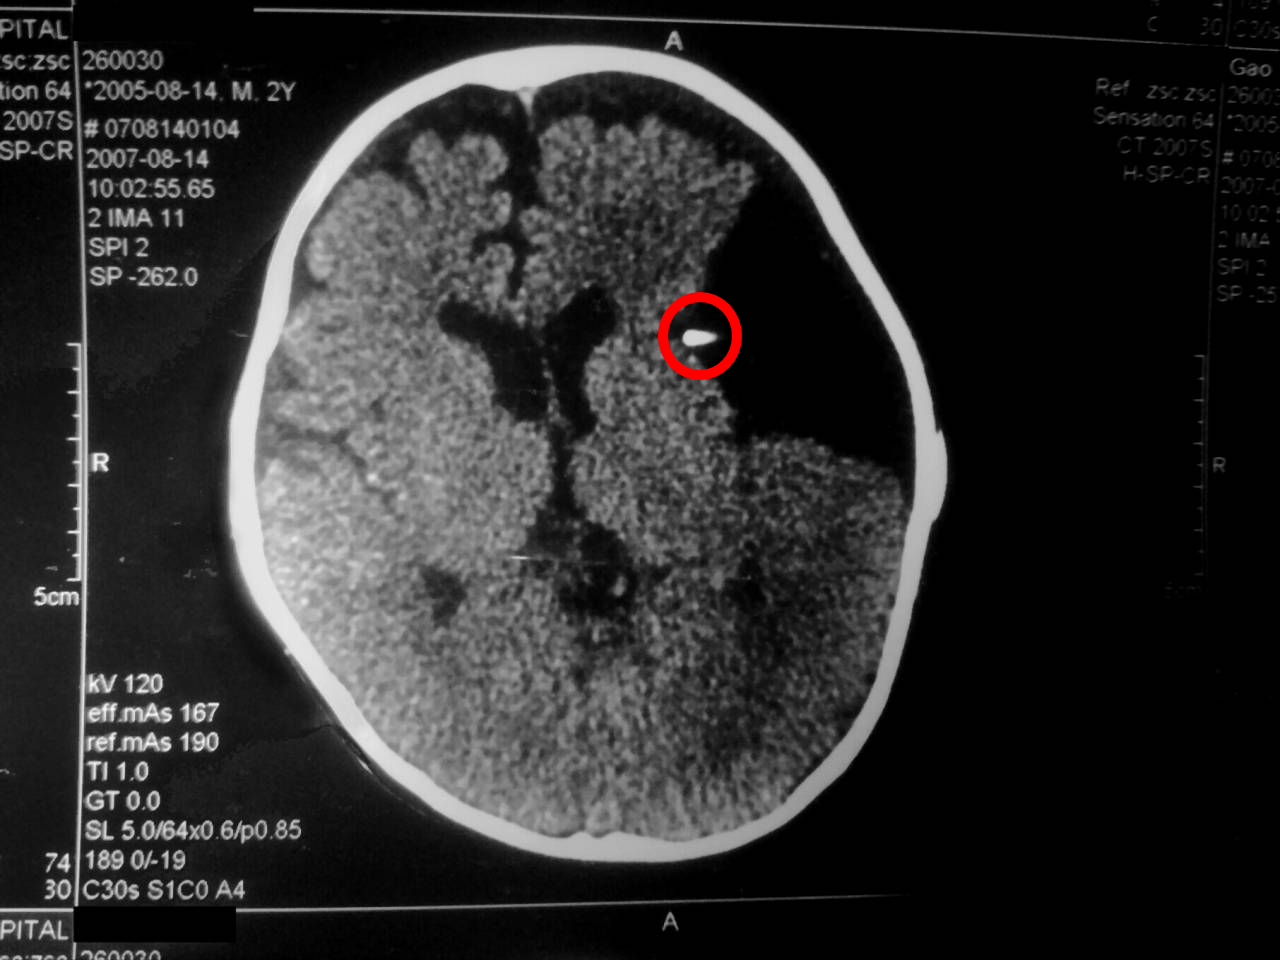

站点医师Moring所摄受到项目异常影响的前SCP-CN-1764负责研究员的脑部CT成像,该研究员已被处决

铲除后或处决SCP-CN-1764-1所得的SCP-CN-1764植株按照基金会标准生物异常-植物异常残余物处理程序Ver.1.6进行处理。处理过程中操作人员需配备标准认知危害护目镜,并在处理完成后一小时、一周、一个月时各进行一次颅脑CT检查。若CT成像显示参与处理SCP-CN-1764植株的人员脑部有约1.2-1.8mm的未知非病变引起的类球状物,或在例行员工体检时发现该人员显现中度的逆模因效应时,该人员需被立即以同排查工作中的处决方式处决,尸体完全焚化。